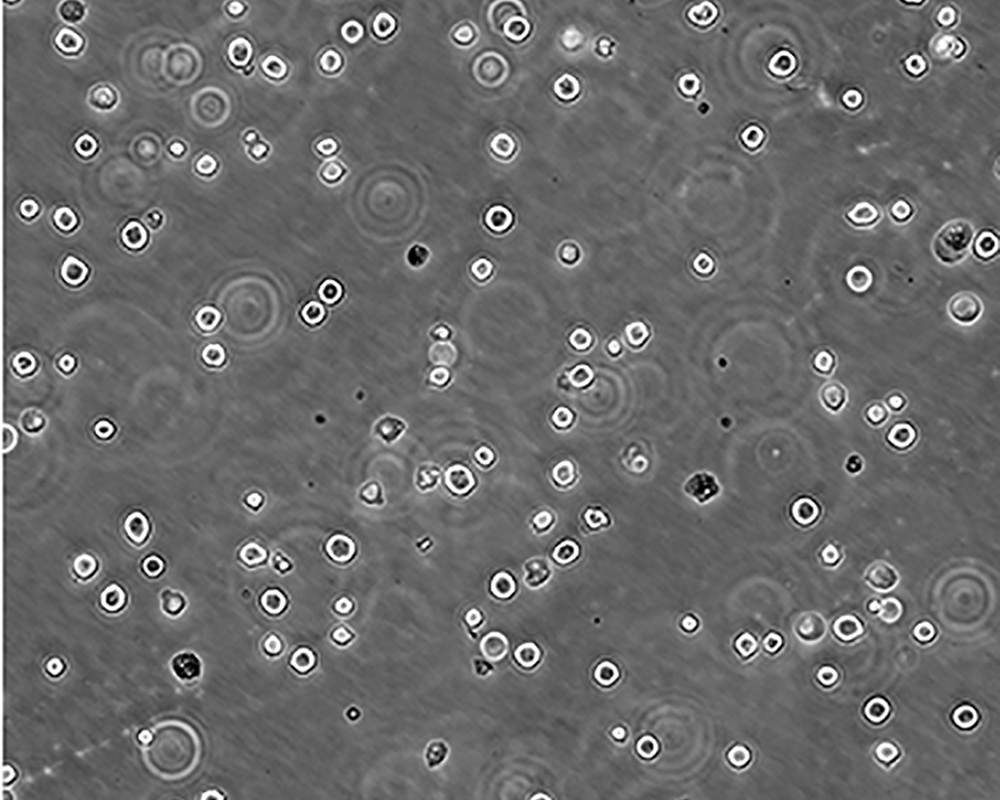

生長(zhǎng)特性 suspension

形態(tài)特征 lymphoblast

細(xì)胞描述 The cell population has been characterized as highly undifferentiated and of the granulocytic series. Studies conducted by Anderson, et al. , on the surface membrane properties led to the conclusion that the K-562 was a human erythroleukemia line. K-562 blasts are multipotential, hematopoietic malignant cells that spontaneously differentiate into recognizable progenitors of the erythrocytic, granulocytic and monocytic series. The effect of inducers on sublines derived from the original K-562 cell line have been reviewed by Koeffler and Golde. Karyological studies on various K- 562 sublines have been classified into three groups(A,B,C) by Dimery, et al. The strain obtained by the ATCC most closely resembles the B population. Occurrence of the Philadelphia chromosome, however, was of much lower frequency; none detected in 15 metaphases examined. The line is EBNA negative.